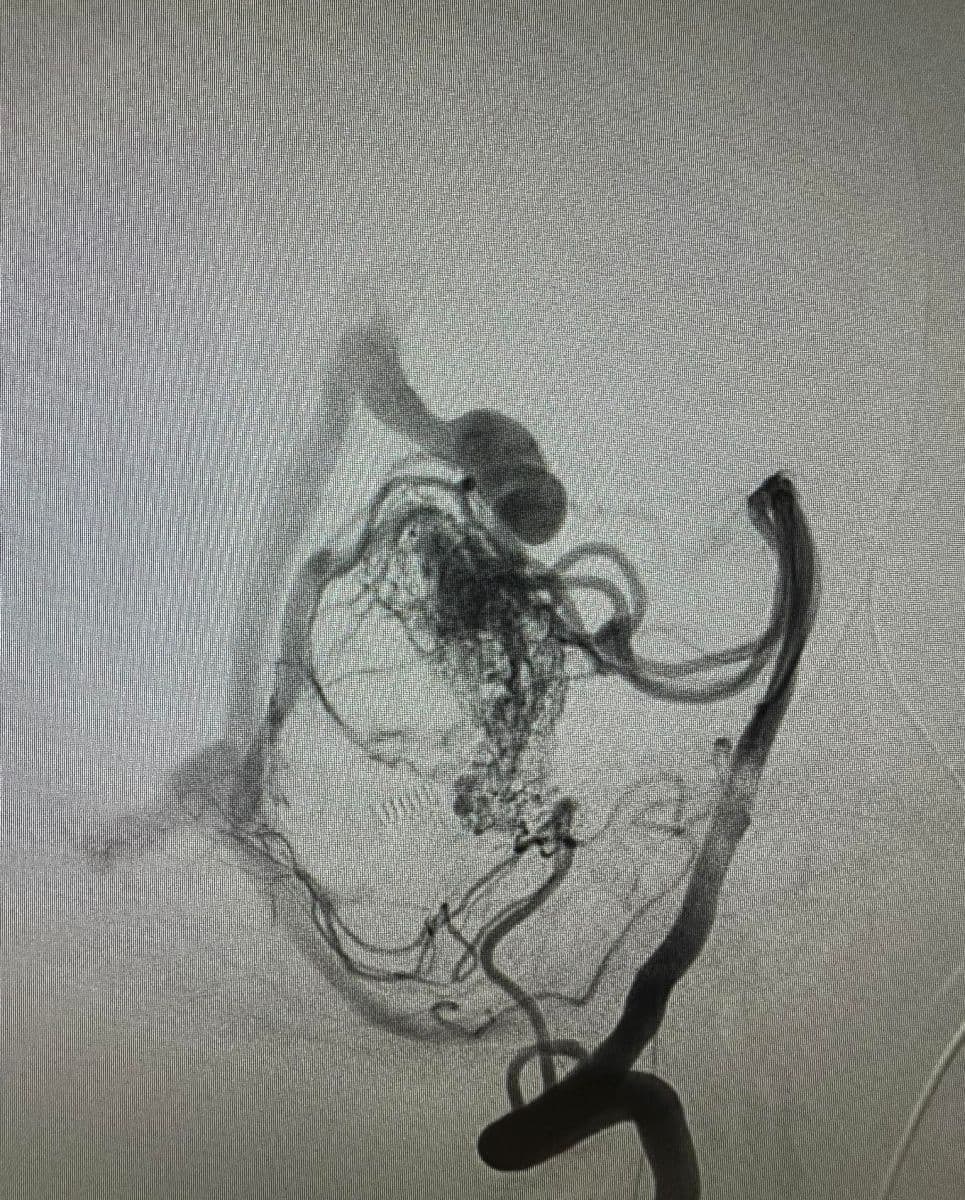

Δια ζώσης συμμετοχή των φοιτητών του Πανεπιστημίου Πατρών σε εξειδικευμένες τεχνικές ενδοαγγειακής αντιμετώπισης αγγειακών δυσπλασιών του κεντρικού νευρικού συστήματος.

Στην επέμβαση συμμετείχαν ο Καθηγητής Ενδοαγγειακής Νευροχειρουργικής Κος Β. Παναγιωτόπουλος, ο Καθηγητής Επεμβατικής Νευροακτινολογίας κος Π. Ζαμπάκης, ο επιμελητής επεμβατικής ακτινολογίας κος Μ. Θεοφάνης και ο αναισθησιολόγος κ. Γούδας.